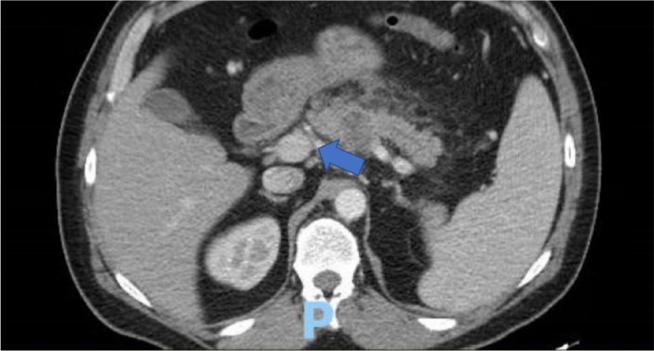

Pancreatic signet ring cell carcinoma (PSRCC) is a rare and aggressive subtype of pancreatic cancer with a dismal prognosis. We present the case of a 50-year-old male who, within six weeks, developed a pancreatic mass with liver metastases. Endoscopic ultrasound-guided biopsy confirmed PSRCC. The presentation of this tumour with distant metastasis after a negative computed tomography (CT) of the abdomen and pelvis six weeks prior underscores the highly aggressive nature of PSRCC and the crucial need for heightened clinical suspicion, especially in cases with persistent or atypical abdominal pain. This case highlights the limitations of current diagnostic modalities and emphasises the urgent need for further research into improved early detection methods, molecular characterisation and effective treatment strategies for this rare and lethal subtype of pancreatic cancer.

Learning points: Aggressive malignancy can become metastatic within six weeks of a negative CT scan.A CT scan may not detect a small pancreatic lesion <2 cm.